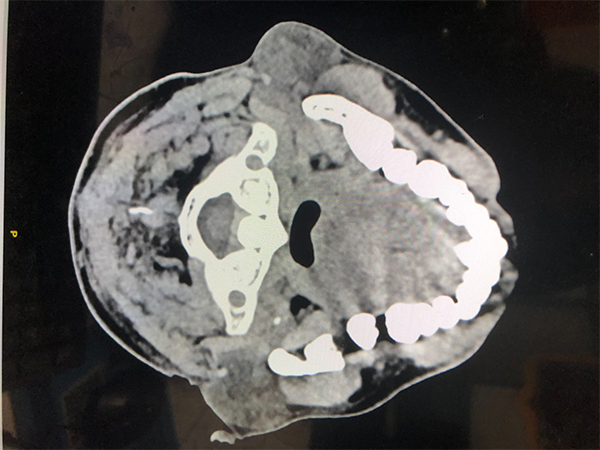

李家鋒主任醫(yī)師團隊成員在術(shù)前對患者病情進行了全面評估,通過詳細的影像學檢查,制定了個性化的手術(shù)方案。

患者在全麻下,由李家鋒主任醫(yī)師主刀,鮑強、曹焜副主任醫(yī)師及石利新醫(yī)師協(xié)助完成手術(shù)。通過單個發(fā)際線切口鈍性分離,免充氣建腔,建立起皮下操作空間。術(shù)中探查見腫物與耳大神經(jīng)及面神經(jīng)關(guān)系密切,操作過程必須極為精細。醫(yī)療組醫(yī)師精準定位腫瘤,在腔鏡的引導下,沿著腫瘤邊緣仔細分離周圍的腮腺組織,利用腔鏡器械及超聲骨刀器械,在不損傷神經(jīng)的前提下,逐步將腫瘤與周圍組織完整分離。充分止血后,留置引流管一根,使用美容縫線確保切口愈合后疤痕最小化。